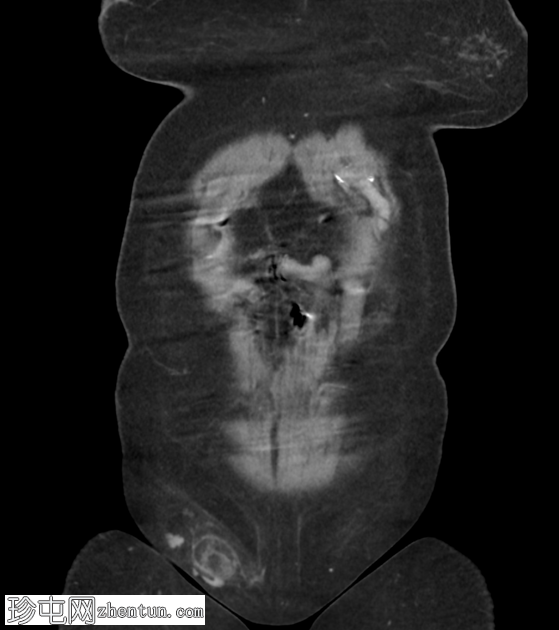

超声检查

右腹股沟可见一边界不清、异质性、略呈强回声的局灶性病变,大小约3.5 x 2.5厘米,伴有少量积液。病变内部及周围血管分布均匀。周围可见脂肪条带,以及少量腹股沟淋巴结轻度肿大。

检查结果提示嵌顿性右腹股沟疝,内含脂肪。建议结合临床表现进行进一步评估。